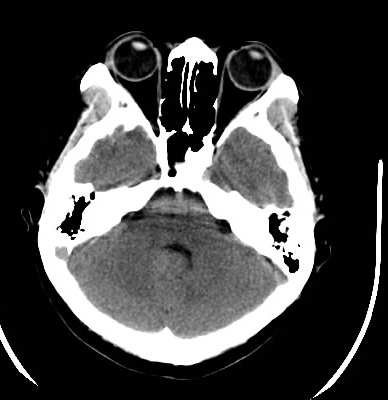

脑外伤患者,无外伤性改变

病灶不规则,呈散在分布,结合外伤病史,考虑气颅可能性大!

平均ct值 -60hu

小乔(楼主)说:平均ct值—60hu。考虑脂肪瘤。

ct值-60应考虑:脂肪瘤.

颅内脂肪瘤系因隶属于中胚层的脂肪掺合进正在关闭的神经管之中,绝大多数见于胼胝体膝部,肿瘤较小;偶尔可发生在整个胼胝体,肿瘤较大。颅内脂肪瘤也可见于四叠体池,鞍上池,大脑脚池以及桥小脑角池。约有50%的中线脂肪瘤并有胼胝体发育不全,但是,胼胝体发育不全很少并有脂肪瘤。胼胝体脂肪瘤有症状的仅占一半,主要为癫痫,痴呆,头痛,半身不遂。癫痫系因脂肪瘤使邻近的纤维性结缔组织浸润到周围脑组织所致。脂肪瘤占位效应不明显,由于它浸润性生长,有时可造成对邻近血管如大脑前动脉的包绕,可影响正常脑脊液通路而导致脑积水。

既然ct值为-60hu,当然首先考虑脂肪瘤,除此之外,我们还应该注意四脑室改变,建议增强扫描

颅内脂肪瘤少见,占颅内肿瘤的1%以下。有人认为不是肿瘤,而是原始脑膜组织的畸形。好发于胼胝体及其周围。胼胝体区脂肪瘤多并发于胼胝体发育不良。瘤体呈圆形或分叶状,大小不等,境界清楚。ct上,病灶呈脂肪密度的圆形或分叶状肿块,周边可见弧形钙斑。无瘤周水肿。无强化。本例发生于胼胝体区低密度肿块,ct值-60,应是典型的胼胝体区脂肪瘤。